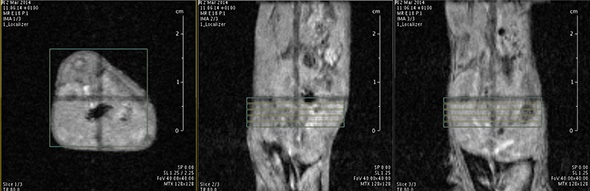

I think that also the low-field, let’s say the low/intermediate field to work at the 1 Tesla for instance as in the case of this beautiful Icon system, this gave us unique possibilities. Anytime we use a gadolinium-based agent or more in general a paramagnetic basic agent the best field is the 1 Tesla.

So, we can show that there is a real advantage of working at 1 Tesla in comparison to for instance 7 or 9 Tesla when one is using a relaxation enhancer to target a specific epitope in the region of interest.